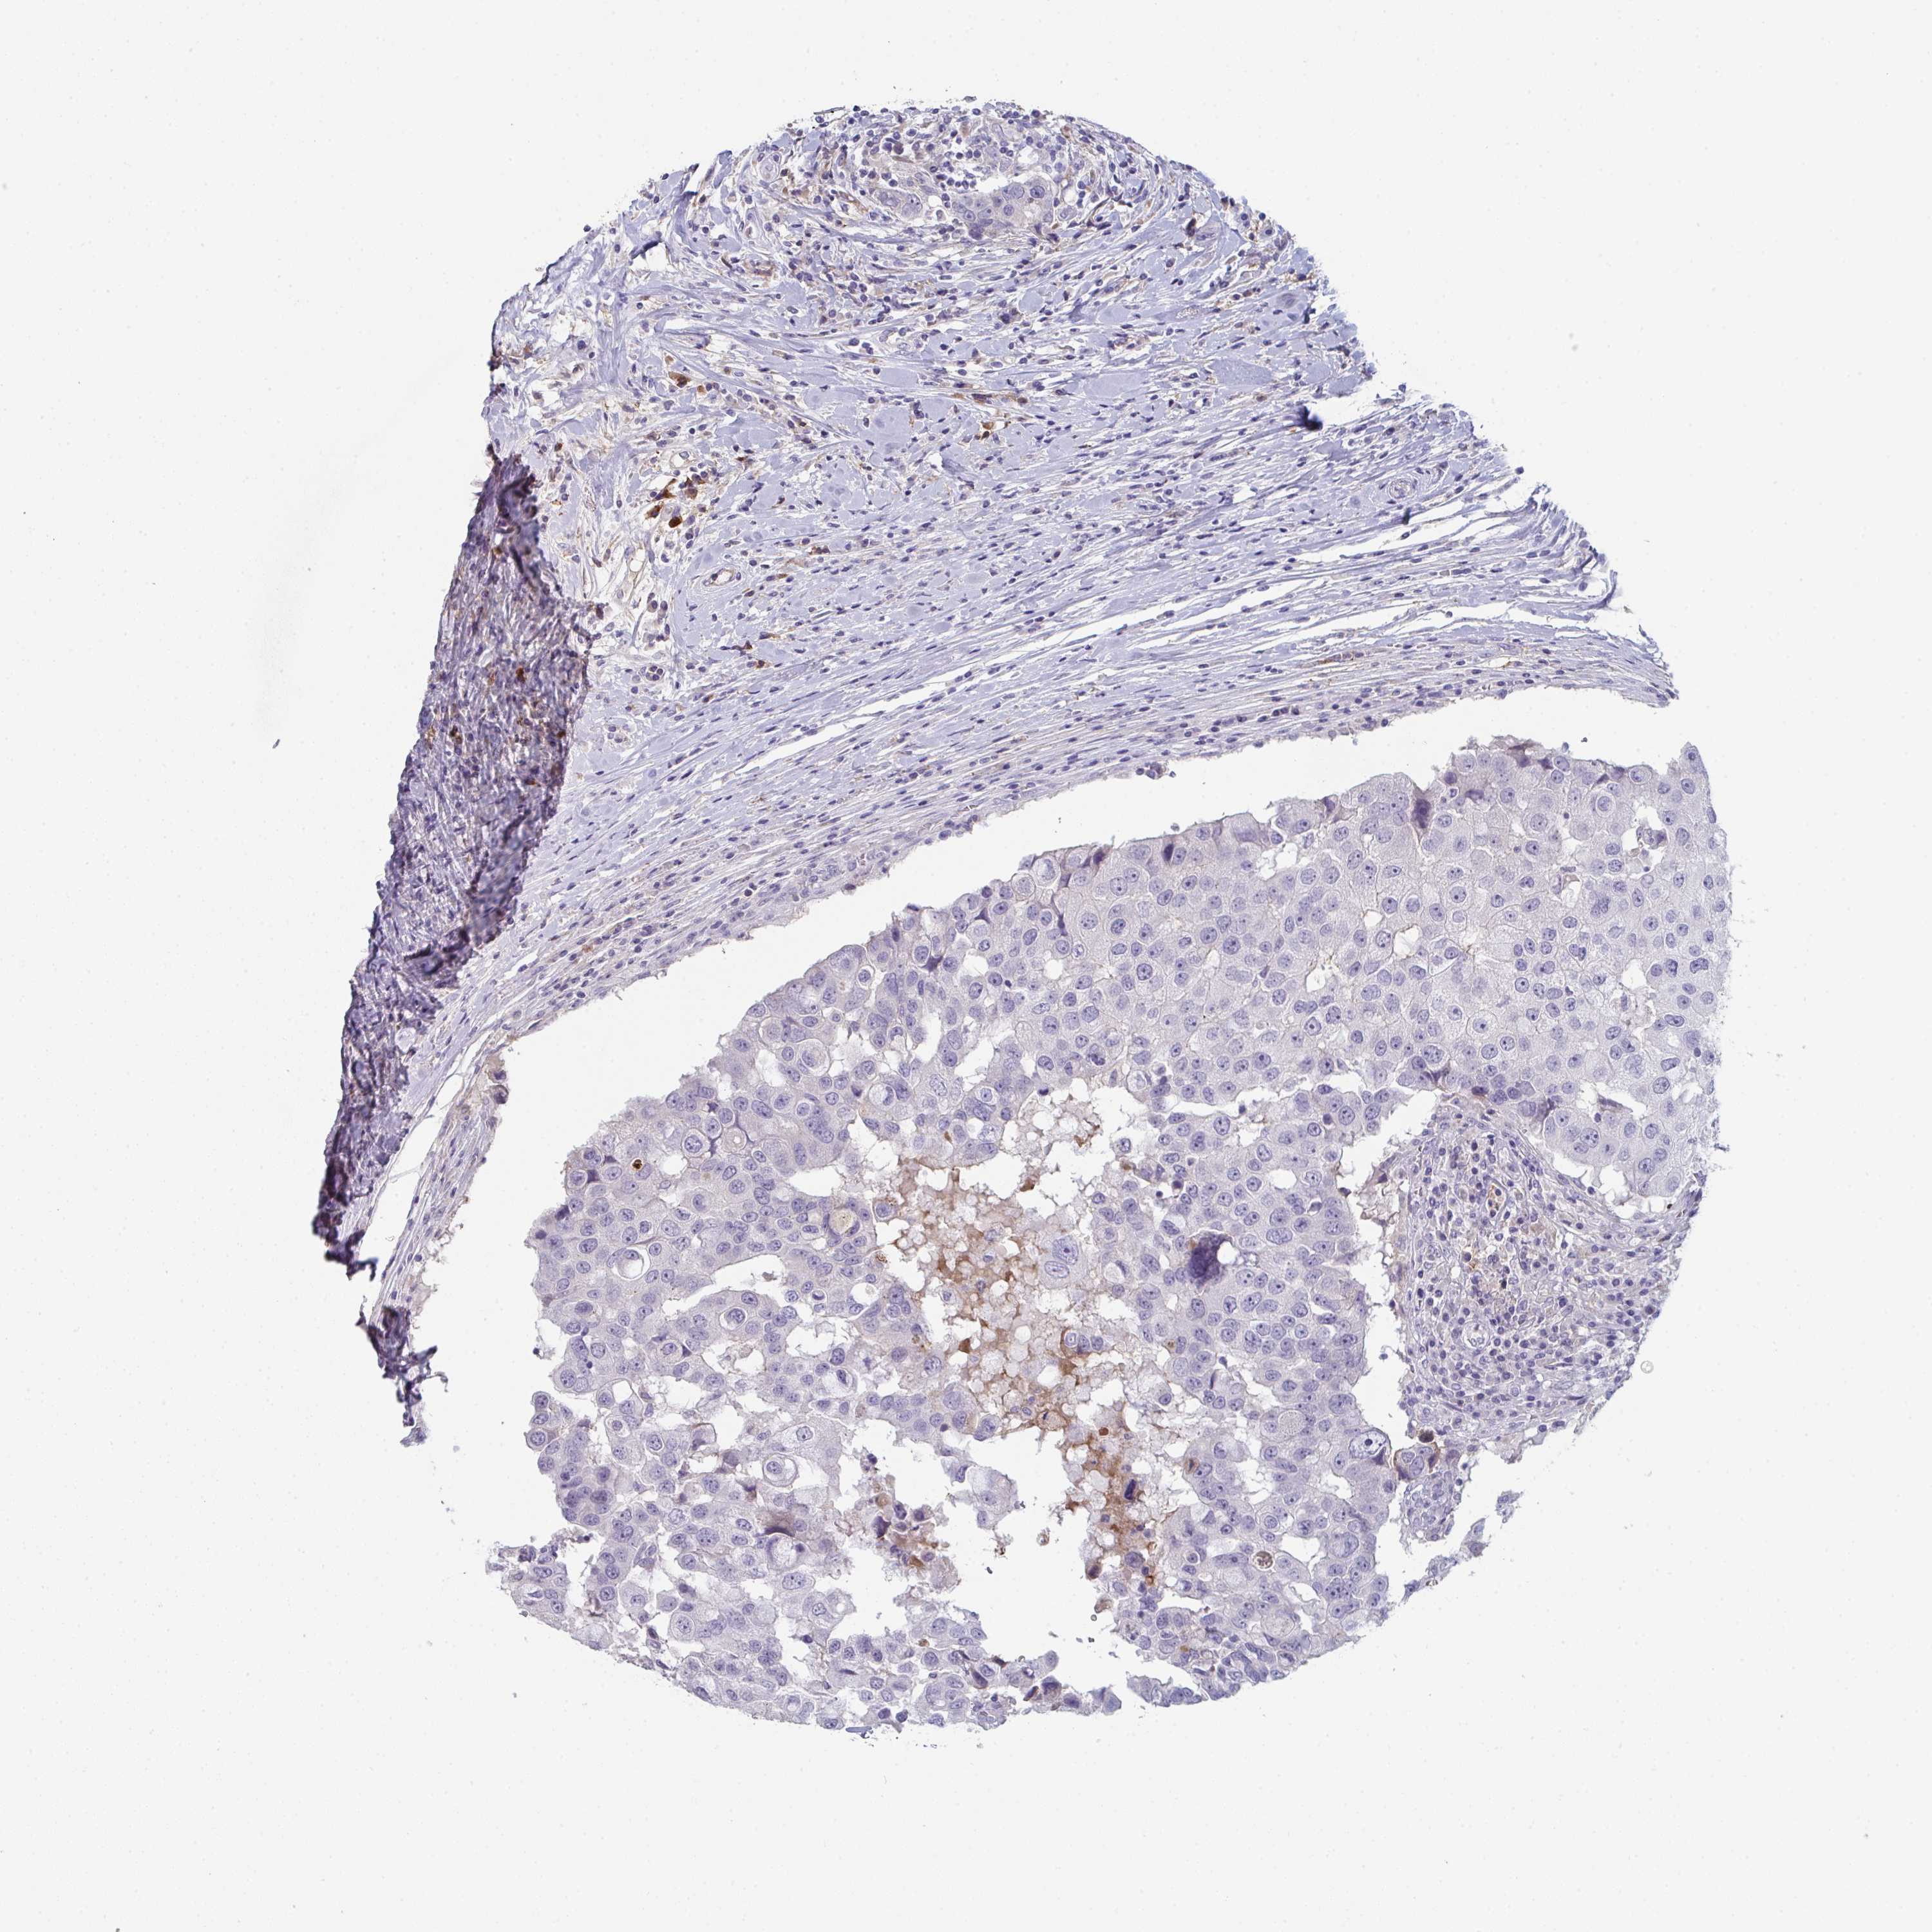

BRCA TCGA BRCA VALIDATION PROTEIN EXPRESSION

ANTIBODIES

AND

VALIDATION